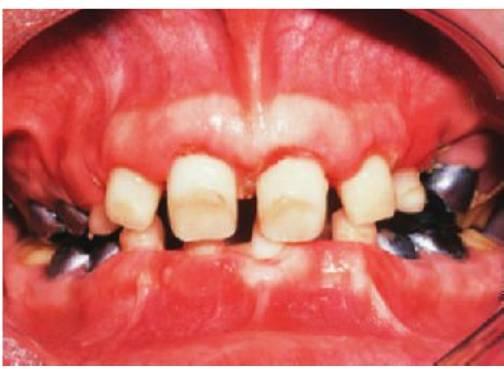

- Varios dientes ausentes (fig. 9.1 B).

Los dientes son pequeños y cónicos y a menudo presentan un gran diastema anterior (fig. 9.3). Sus manifestaciones pueden limitarse a un solo diente ausente o a un incisivo lateral en clavija (v. hipótesis de Lyon, más adelante) y las mujeres heterocigóticas suelen ser diagnosticadas gracias a este tipo de dentición.

Dentro del grupo de displasias ectodérmicas, se observan asimismo modos de herencia autosómica tanto dominante como recesiva. Si se compara con la displasia ectodérmica hipohidrótica ligada al cromosoma X, en las familias con este trastorno no existen diferencias tan acentuadas en cuanto al grado de trastorno entre los hombres y las mujeres (figs. 9.2A, 9.4). Se han identificado mutaciones en el gen MSX1 (4p16.1) en familias con terceros molares y segundos premolares ausentes con o sin paladar hendido/labio leporino, así como en familias con el síndrome diente-uña (Witkop). Se han observado mutaciones del gen PAX9 (14q12-q13) en otras familias con dientes ausentes de forma autosómica dominante.